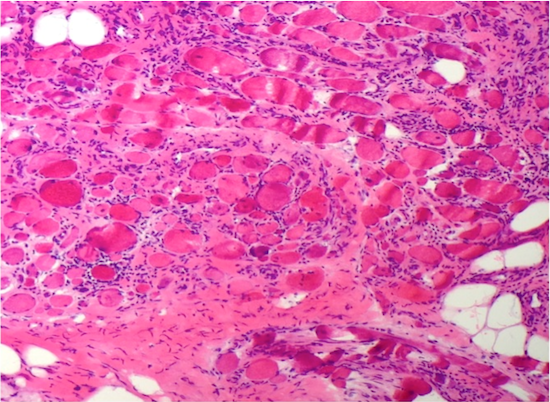

Microscopic (histologic) description

- Variation in myofiber sizes with small angulated myofibers, either individually or in groups

- Hypertrophied myofibers can also be seen

- An increase in internal nuclei (normal muscle can have up to 3% of myofibers having internal nuclei) can be seen

- There can be a brisk inflammatory response including CD8+ lymphocytes, which may invade non-necrotic myofibers

- Occasional myofibers undergoing phagocytosis by CD68+ macrophages can be identified

- Regenerating, basophilic myofibers can be seen

- The Gomori Trichrome stain shows "rimmed vacuoles", although the extent of myofibers having classic rimmed vacuoles varies (Dubowitz: Muscle Biopsy: A Practical Approach, 2013, 4th Edition)

- The vacuoles disrupt the myofiber architecture and can lack NADH-TR staining (Dubowitz: Muscle Biopsy: A Practical Approach, 2013, 4th Edition)

Microscopic (histologic) images